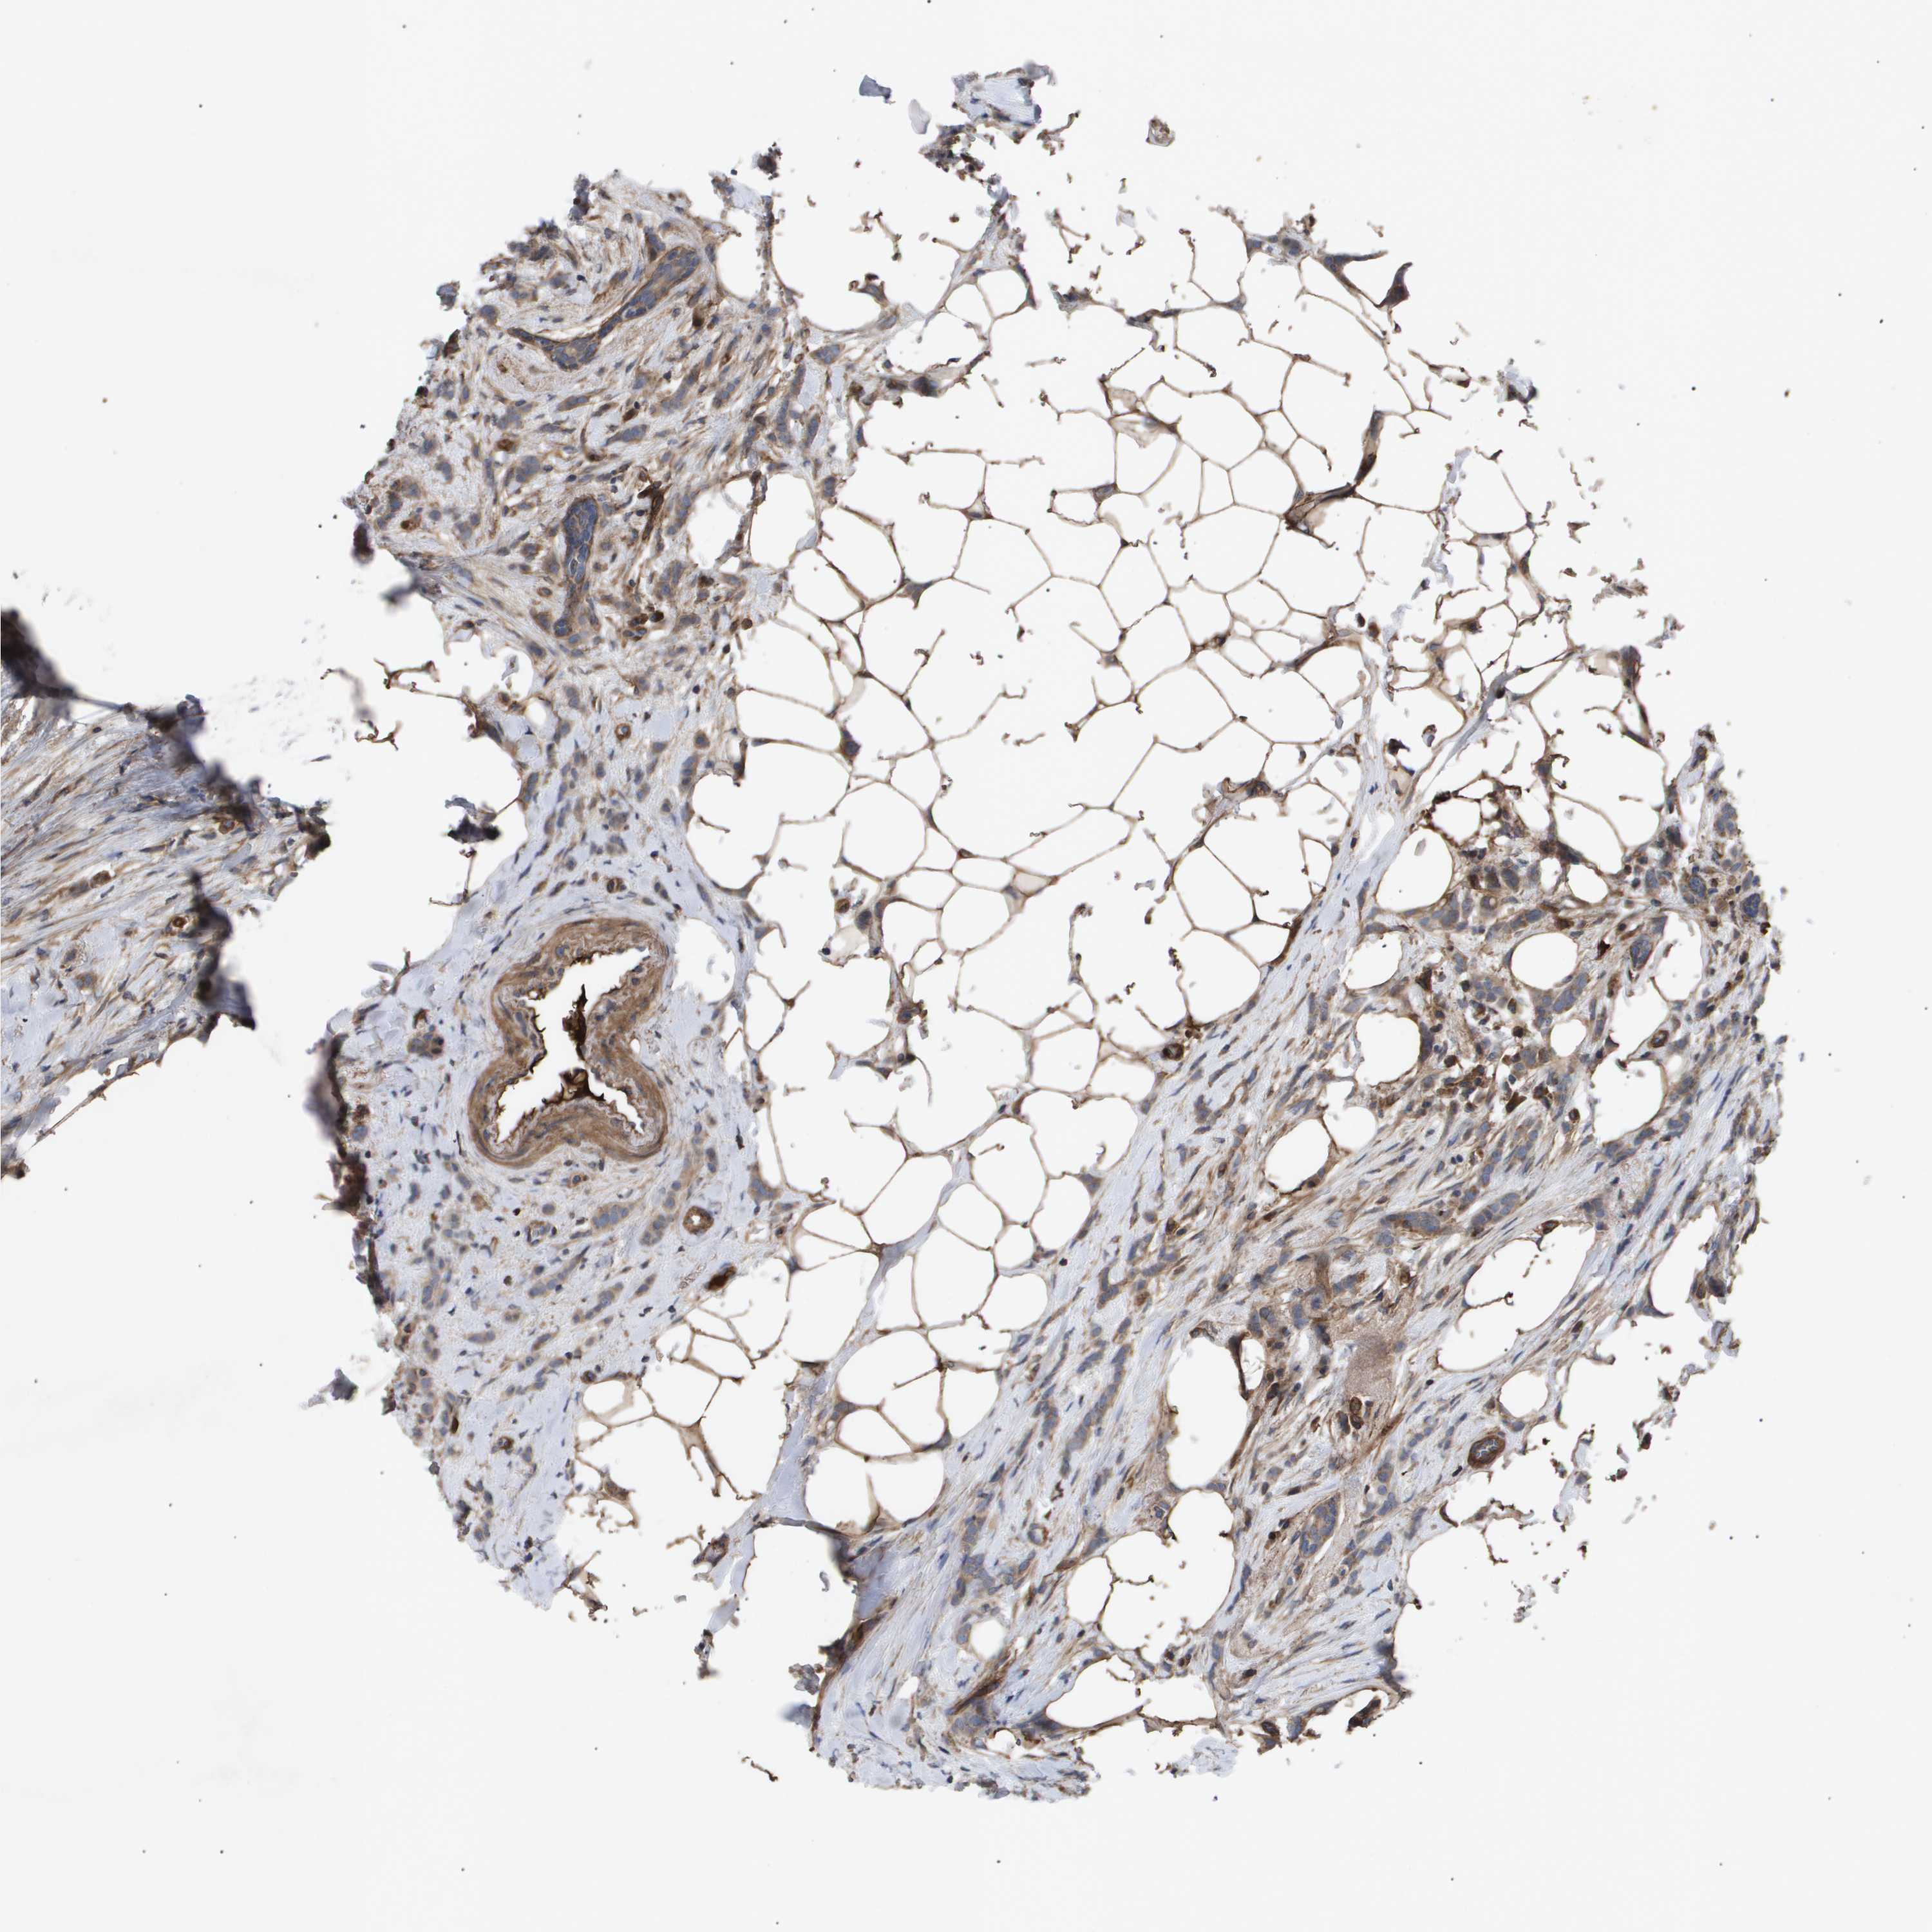

CANCER BREAST CANCER Show tissue menu

BRCA TCGA BRCA VALIDATION PROTEIN EXPRESSION